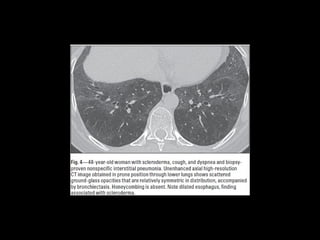

DD UIP CT •AR, Esclerodermia (esófago dilatado) • Asbestosis ( derrame pleural, bandas parenquimatosas) • Neumonitis por hipersensibilidad crónica: fijarse en signos de atrapamiento aéreo, Respeto de bases o cuando hay nódulos centrolobulillares. • Sarcoidosis terminal: fibrosis en segmentos posteriores de lóbulos superiores o perihiliar, o nódulos perilinfáticos. • NSIP • Complicaciones: • Exacerbación, DAD • Cáncer pulmonar 10-15% bases

• 22.

NSIP • + asociadoa otras condiciones esclerodermia, poliomiositis, dermatomiositis, toxicidad a drogas, inmunodeficiencia. • Mejor pronóstico • 40-50 h=m

• 23.

NSIP Histología • Continuode componente celular a fibrosis • Plasmocitos y linfocitos • Engrosamiento intersticial por acumulación de colágeno • Homogeneidad • Biopsia es incompatible con otros patrones

• 24.

NSIP TC • Vidrioesmerilado bilat y simétrico, LS Reticulación fina, BQ por tracción, disminuciónd e volumen pulmonar, panalización leve Consolidaciones Exacerbaciones menos comunes que FPI • Pronóstico depende del grado de fibrosis • Celular: 100% sv Fibrótico: 5 años SV